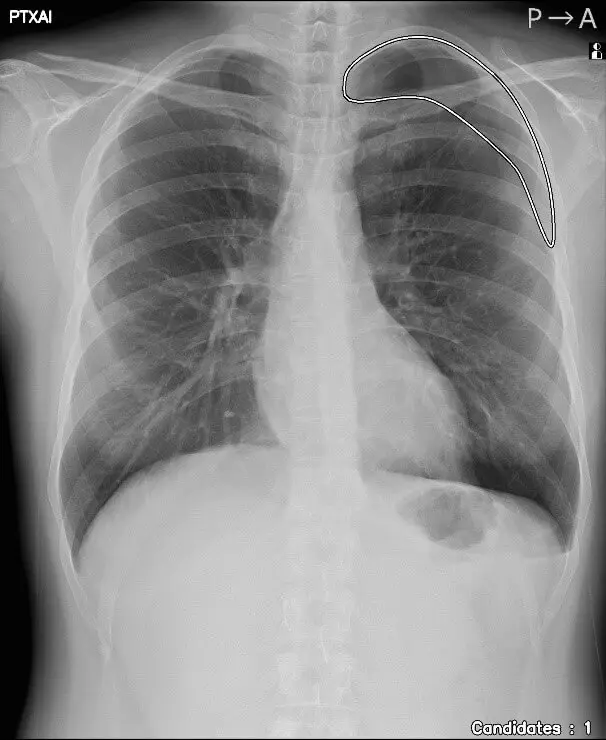

人のレントゲン写真 気胸の検出領域を表示

気胸の検出領域を表示

「CXR Finding-i 気胸検出タイプ」は、胸部単純X線画像をAI※2で解析することで重要所見である気胸の候補を迅速に検出し、候補領域を画像上に表示することで見落とし防止を支援します。病変検出性能を示す指標である感度※3は95%と高い水準を実現していることに加え、気胸が存在しない画像をAIが正しく陰性(気胸なし)と判断した割合を示す特異度※4は96%であり、病変を見逃さないようにしつつ偽陽性も抑制した高精度の検出性能が特長です。